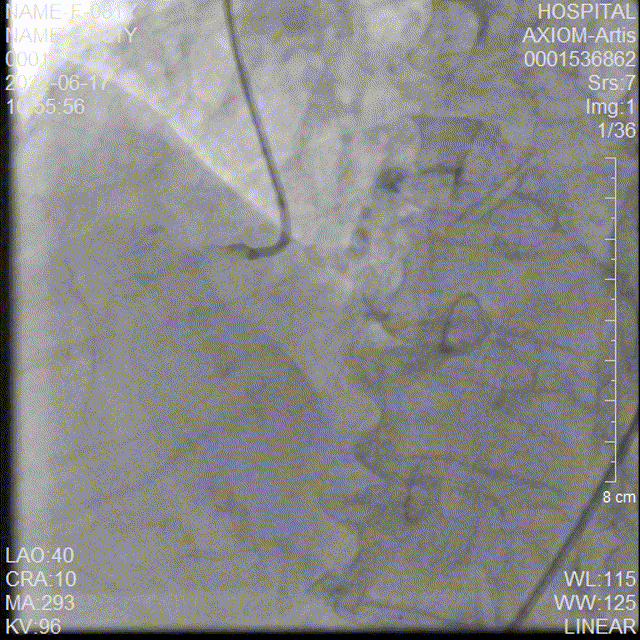

20mm球囊后扩

后扩后造影

本例手术为Type1型二叶式主动脉瓣重度狭窄合并中量返流的高龄心衰患者,重度钙化且分布不均匀,右冠窦内钙化向左室流出道衍生,左室流出道呈敞口形态,术中瓣膜释放过程中多次出现下滑,黎文生教授TAVR团队通力配合、全面细致评估,充分利用TaurusElite瓣膜系统优异的多次可回收功能,在瓣膜释放至工作位时多角度评估瓣膜植入深度、锚定力以及冠脉灌注情况,最后瓣膜释放定位位置接近瓣环。为使患者获益更佳,决定使用20mm球囊后扩改善瓣膜展开形态及组织贴合情况。

术后行主动脉根部造影检查与经食道超声影像评估,无瓣周漏,瓣膜形态良好,跨瓣压差由术前的107 mmHg即刻下降为0 mmHg,TaurusElite植入圆满成功!